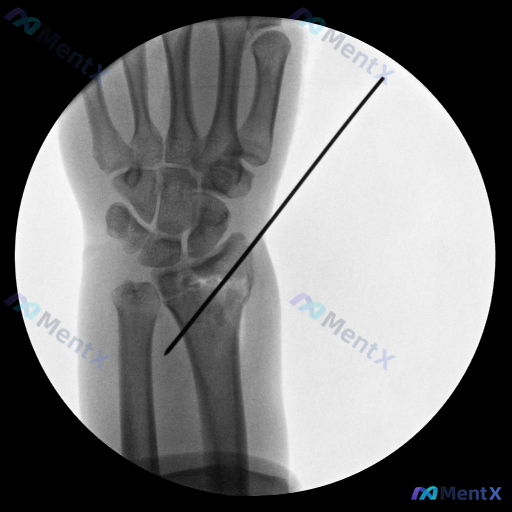

整理到一张左侧腕关节正位X光片的影像资料,背景是患者有舟骨内固定手术史。 主要影像表现: - 左侧舟骨腰部可见一枚金属螺钉内固定影,螺钉穿透舟骨长轴,位置尚可 - 舟骨形态大致连续,未见明显新鲜骨折线 - 桡骨远端、尺骨茎突及其余腕骨轮廓清晰,未见明显骨折或脱位 - 桡腕关节、下尺桡关节间隙尚可,腕...